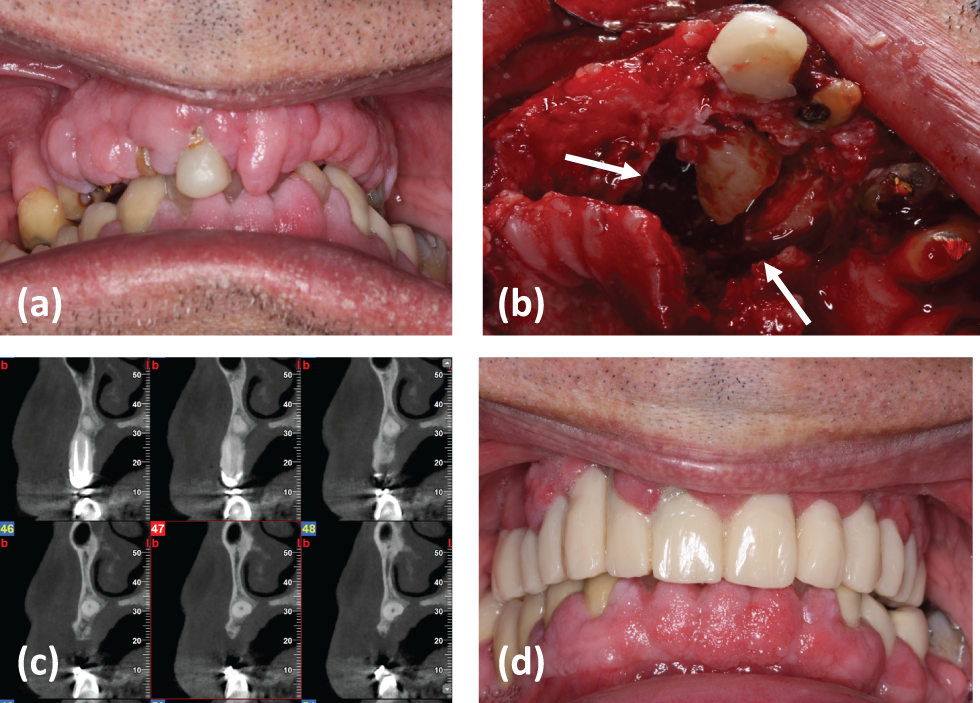

Another 55-year-old smoker male patient with an impacted canine and need for dental implant rehabilitation was also referred to the practice. The patient’s medical history was clear and he was scheduled for dental implant placement. It was also decided not to remove the ankylosed tooth, since placement of the dental implants could not be carried without damage to impacted teeth (Figs. 3a,3b). The patient refused the construction of a fixed partial denture, because he preferred a conservative treatment without his tooth being prepared, taking his consistency with periodontal supportive treatment into consideration.

Fig. 3. A 55-year-old male patient presented for total mouth rehabilitation: (a) Radiographic evaluation revealed tooth impaction of #13, (b) Additional cbct shows the location of #13, (d) Dental implant placement in proximity with the root of the impacted tooth, (e) and (f) final dental implant restoration of #13, 14.

One of the dental implants- #13- was placed in contact with the PDL and cementum of the impacted tooth assuming that no damage to the pulp tissue would be created based on the current literature and since the osseointegrated surface of the dental implant could not be reduced significantly (Figs. 3c3e) [9]–[12].

Case 4

A 55-year-old non-smoker female patient was presented to the practice for tooth replacement #52. (Fig. 4) The deciduous tooth was extracted due to root resorption and increasing mobility. Tooth #12 was impacted as revealed by a CBCT (Figs. 4b and 4c). The presence of the PDL was radiographically evident suggesting that the impacted tooth could be moved orthodontically. Moreover, the position of the impacted canine was apical enough for a dental implant to be placed without extracting the impacted tooth. The patient was informed about the various treatment options for the edentulous space of #12 (orthodontical movement of the impacted tooth, dental implant placement, or fixed partial denture). The patient decided to have a dental implant placed in the edentulous space which was done without extracting tooth #13. Since the buccolingual width of the alveolar ridge was not adequate for a dental implant placement, guided bone regeneration was decided to be done before implant placement by the use of a resorbable collagen membrane, allograft and xenograft (Figs. 4d4f). 5 months after bone augmentation CBCT revealed bone formation (Fig. 4h). The dental implant was placed 5 months after the ridge augmentation procedure and the final restoration was done 3 months after implant placement (Figs. 4h4j).

Fig. 4. Patient presents for extraction of #53 and its replacement with a dental implant: (a) and (b) CBCT at the area (c)–(f) Patient is scheduled for guided bone regeneration, with xenograft, allograft and collagen membrane, (h) CBCT 4 months after bone regeneration reveals bone formation at the previous buccal deficiency, and (i) and (j) a dental implant was placed and restored 3 months after placement.